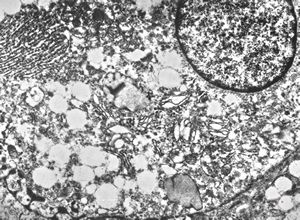

F,25y. | metachromatic leukodystrophy - n. suralis

F,8y. | metachromatic leukodystrophy - n. suralis

F,25y. | metachromatic leukodystrophy - n.suralis